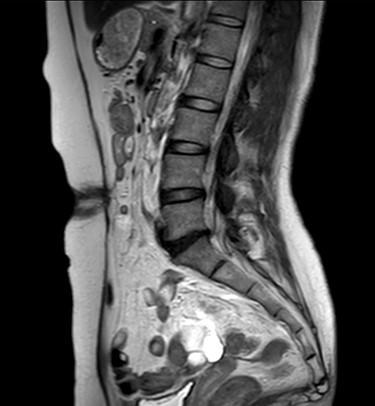

A 47-year-old woman was referred to us by her obstetrician. She developed a PHS after laparoscopic total hysterectomy with right oophorectomy performed 3 years previously. She reported pain with intermittent bulging on the superior aspect of the umbilical region. Clinical examination revealed a single hernia orifice at that location. Her height was 161.1 cm, with a weight of 60.1 kg, yielding a body mass index of 23.16 kg/m2. Her medical history included uterine fibroids and ovarian cysts. She had no history of smoking. Magnetic resonance imaging (MRI) revealed protrusion of adipose tissue at the upper side of the umbilical region, through a fascial defect measuring 9 × 13 mm; diastasis recti was also noted (Figs 1 and 2).

The patient did well after surgery. Follow-up MRI taken 10 days after surgery confirmed the absence of hernia and closure of the fascial defect (Figs 9 and 10).